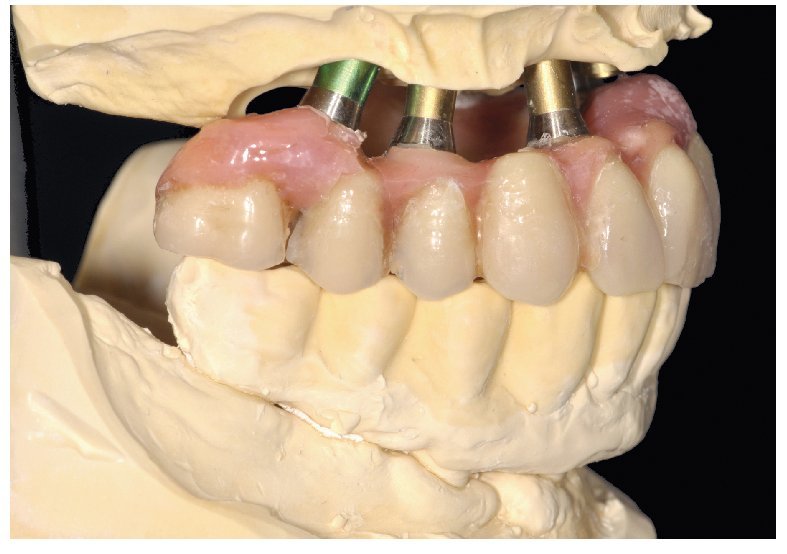

La intervención quirúrgica (figs. 63 y 64) se realizó bajo anestesia local y se trataron al mismo tiempo ambas arcadas dentarias. Durante la primera fase se insertaron seis implantes cónico-cilíndricos (SPI®CONTACT, Thommen Medical AG, Waldenburg, Suiza) en la arcada dentaria superior mediante un acceso sin colgajo. Para ello se utilizaron los pilares pertinentes para reposiciones de puente atornilladas oclusalmente (VarioMulti, Thommen Medical AG, Waldenburg, Suiza) (fig. 65). Tras la intervención quirúrgica se colocó en boca la prótesis provisional prefabricada a partir de los datos de planificación y tallada en las posiciones de implante y se unió a las cofias provisionales (fig. 66 y 67); para ello se utilizó un composite de fraguado dual. Mediante una prótesis provisional mucosoportada se pudo preservar la estructura gingival hasta el momento de la implantación, y con ello la relación correcta entre los maxilares superior e inferior. Para la arcada dentaria inferior se utilizaron implantes cilíndricos (Element, Thommen Medical AG) (figs. 68 y 69). En combinación con los pilares pertinentes para prótesis atornilladas, se procedió aquí de la misma manera que en el maxilar superior. Una vez se hubo alineado oclusalmente la prótesis provisional del maxilar inferior con respecto al superior, se fijó sobre las cofias provisionales (fig. 70); debido a la formación de colgajo no había sido posible la alineación sobre la mucosa. Este procedimiento permite preservar la dimensión oclusal vertical que se definió al principio del tratamiento. A continuación se repasan, se pulen y se envían a la clínica para su incorporación las prótesis provisionales, las cuales, por el contrario, se apoyan exclusivamente sobre los implantes (figs. 71 y 72). Allí tienen lugar el control radiológico y el rectificado oclusal (figs. 73 y 74).

Fig. 69. Los implantes y las cofias provisionales para prótesis atornilladas colocados en el maxilar inferior.

Fig. 70. La prótesis provisional del maxilar inferior se une a los pilares; para ello se alinea a partir de la guía oclusal de la prótesis provisional del maxilar superior.